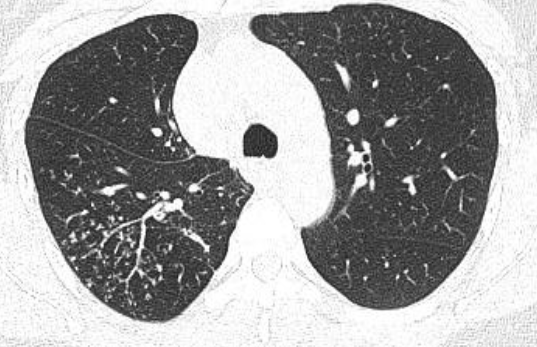

3. 继发性肺结核:继发性肺结核胸部影像表现多样。轻者主要表现为斑片、结节及索条影,或表现为结核瘤或孤立空洞;重者可表现为大叶性浸润、干酪性肺炎、多发空洞形成和支气管播散形成树芽征等;反复迁延进展者可出现肺损毁,损毁肺组织体积缩小,其内多发纤维厚壁空洞、继发性支气管扩张,或伴有多发钙化等,邻近肺门和纵隔结构牵拉移位,胸廓塌陷,胸膜增厚粘连,其他肺组织出现代偿性肺气肿和新旧不一的支气管播散病灶等。

*典型右下叶背段沿支气管播散的树芽征,确诊为肺结核(但仍然需与其他支原体肺炎以及非结核分枝杆菌肺病鉴别)